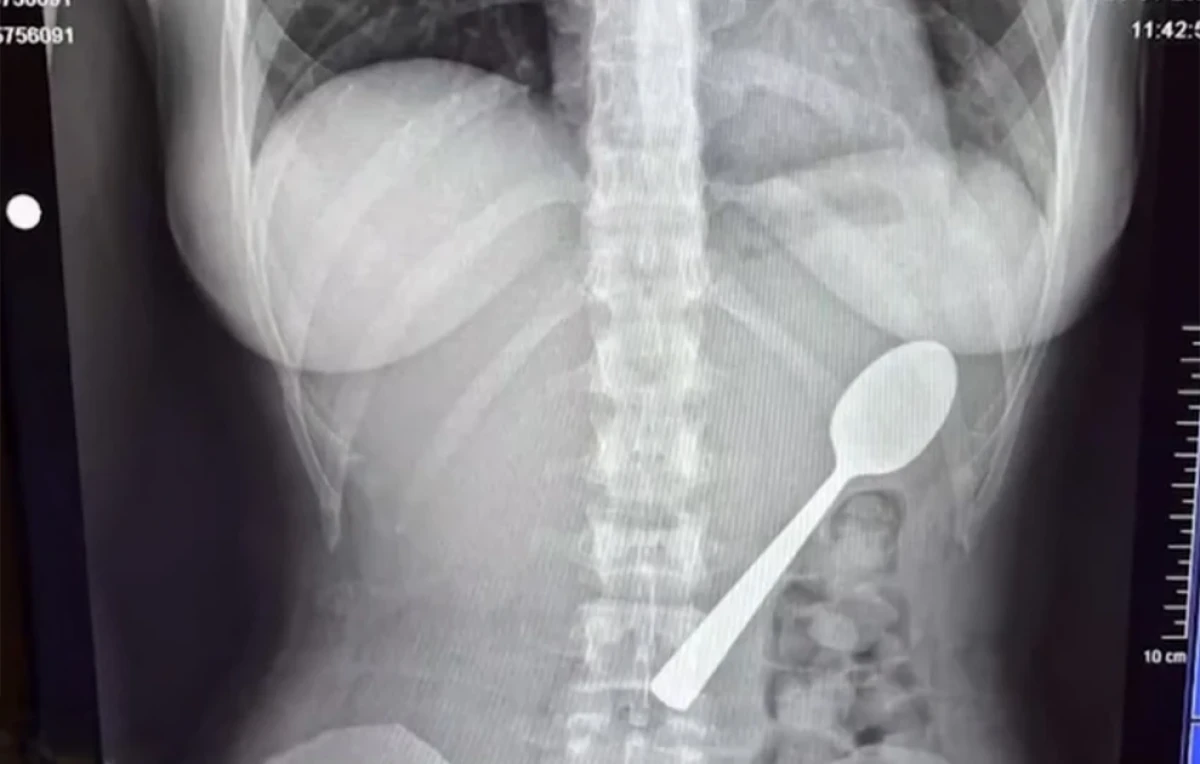

Μια απίστευτη περιπέτεια έζησε μια νεαρή γυναίκα, καθώς κατάπιε ένα κουτάλι 17 εκατοστών, το οποίο κόλλησε στο στήθος της, ενώ νοσηλεύτηκε στα επείγοντα, μόνο κατόπιν διαδικτυακής παρένεσης.

Αρχικά, προσπάθησαν να τραβήξουν έξω το κουτάλι, όμως ήταν αρκετά μεγάλο για να βγει φυσιολογικά, οπότε προχώρησαν σε γαστροσκόπηση.